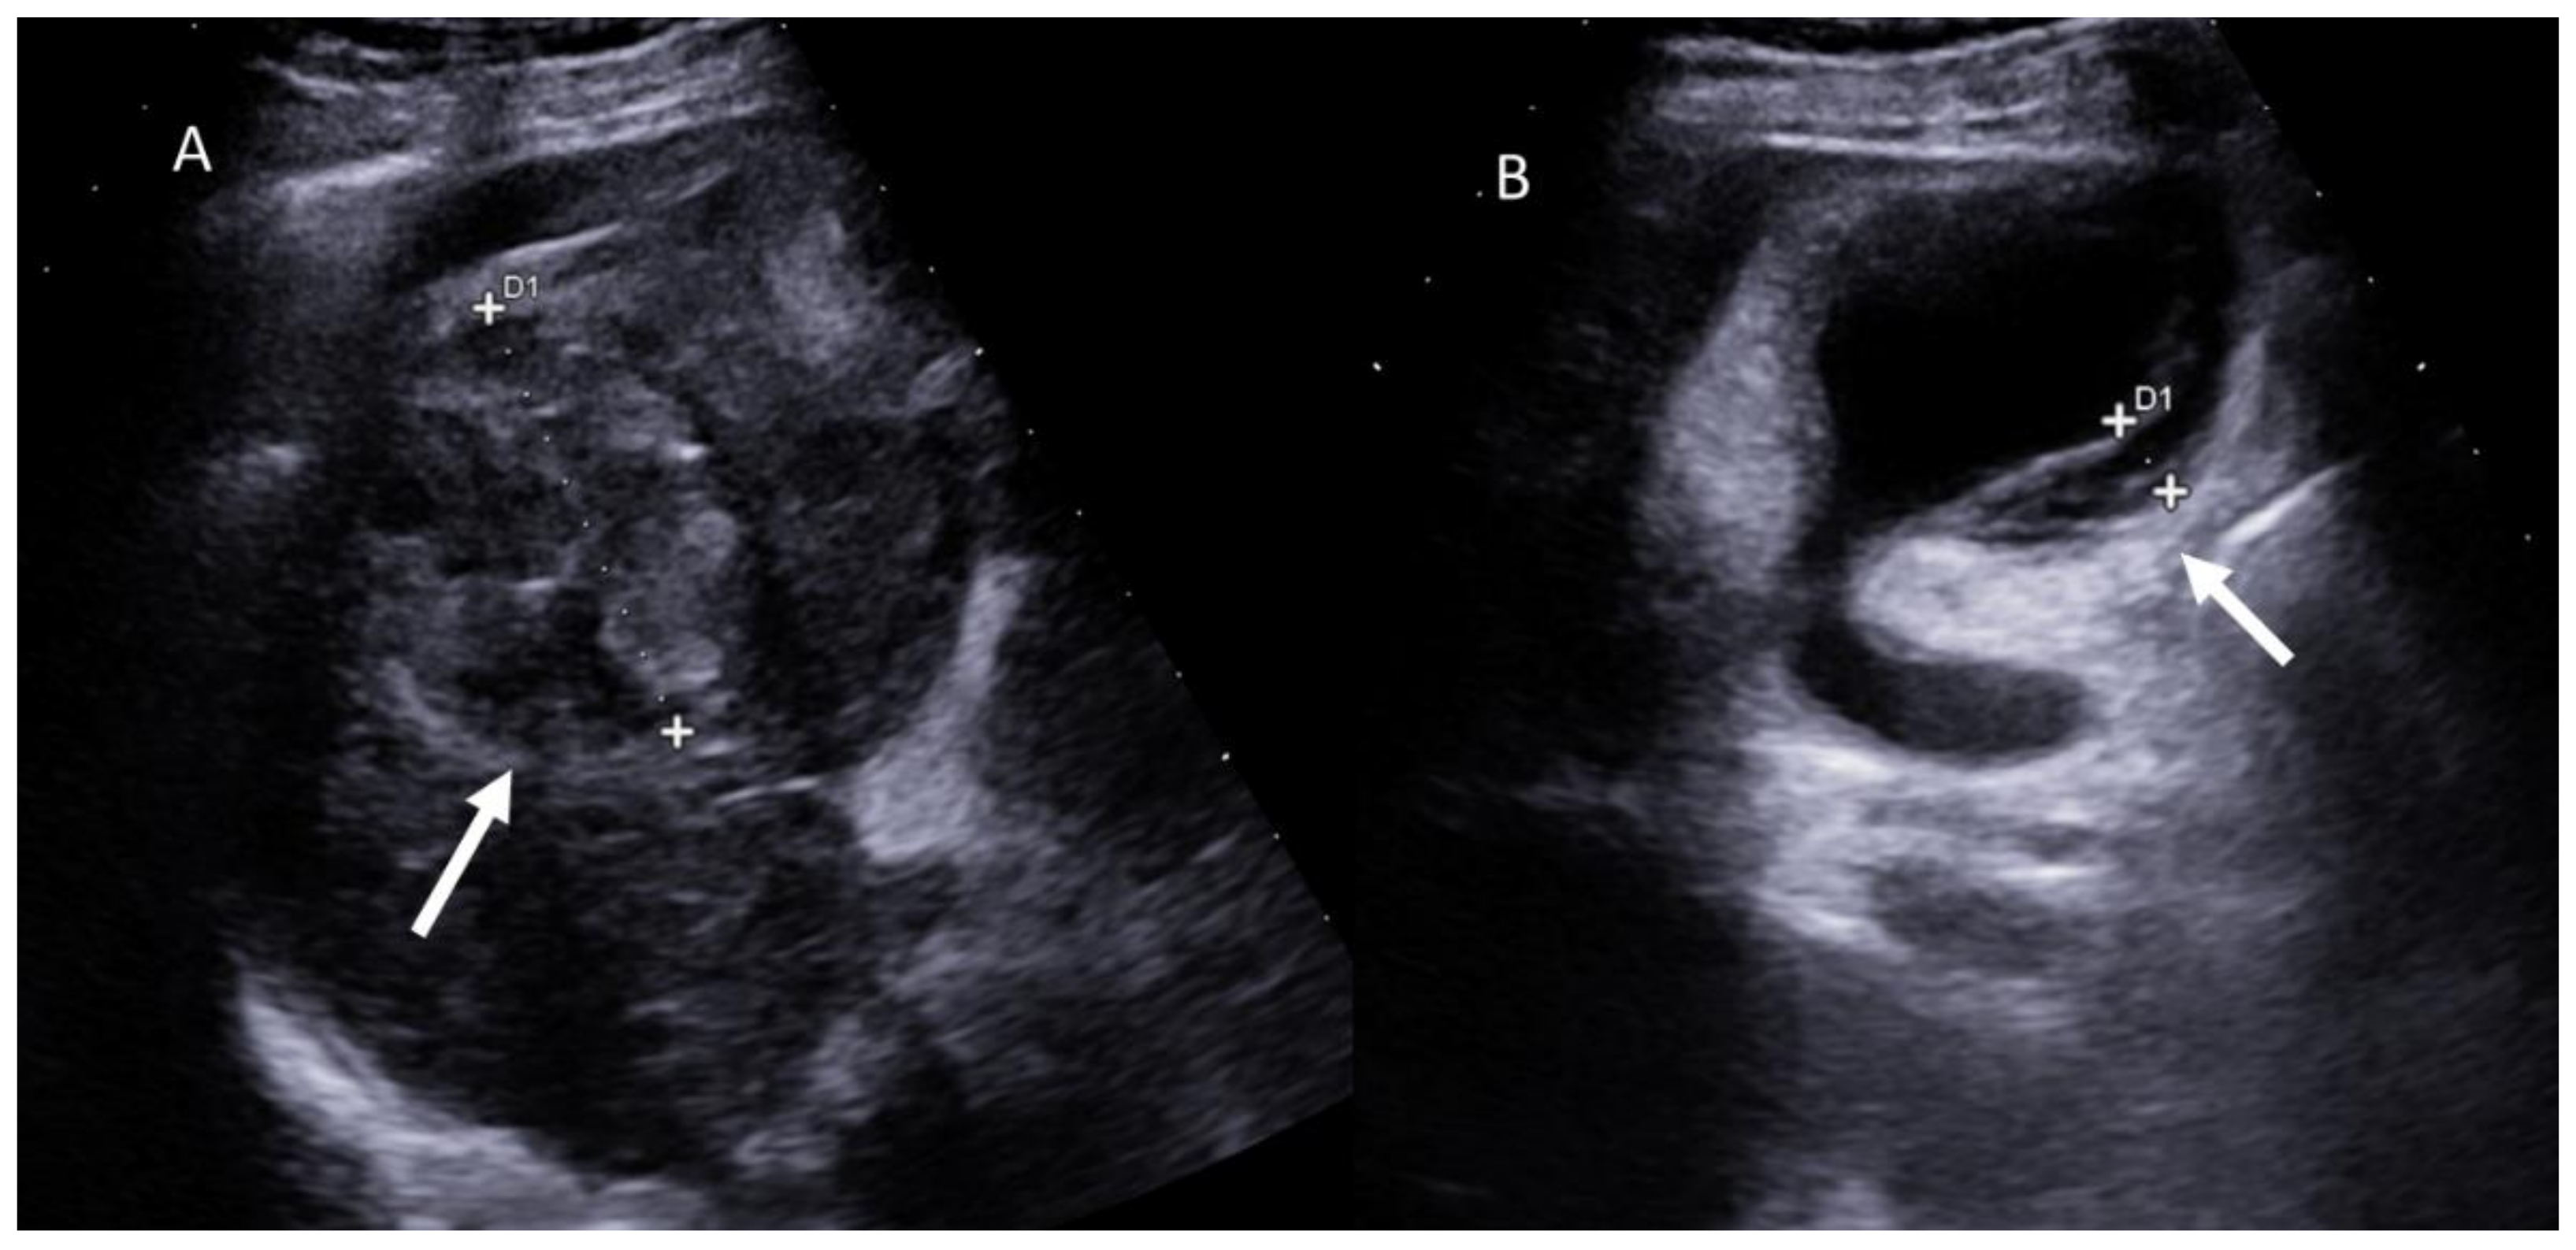

- Battaglia, V.; Cervelli, R. Liver investigations: Updating on US technique and contrast-enhanced ultrasound (CEUS). Eur. J. Radiol. 2017, 96, 65–73. [Google Scholar] [CrossRef]

- Faccia, M.; Garcovich, M.; Ainora, M.E.; Riccardi, L.; Pompili, M.; Gasbarrini, A.; Zocco, M.A. Contrast-Enhanced Ultrasound for Monitoring Treatment Response in Different Stages of Hepatocellular Carcinoma. Cancers 2022, 14, 481. [Google Scholar] [CrossRef]

- Bai, L.; Wang, X.; Shi, S.; Gao, J.; Li, X.; Wang, Y.; Jiang, M.; Zheng, C.; Liu, H. Evaluation of 3D-CEUS in the Recurrence of Liver Cancer after Radiofrequency Ablation. J. Heal. Eng. 2021, 2021, 3123553. [Google Scholar] [CrossRef] [PubMed]